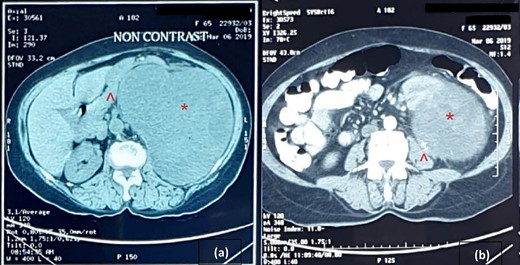

An abdominal ultrasound (US) revealed a 12 × 12 cm solid mass from the left suprarenal area (Fig. 1). Contrasted computed tomography (CT) revealed a 17.5 × 11.5 cm enhancing lesion in the left suprarenal region, completely replacing the left adrenal gland. The left kidney was inferiorly displaced, and coarse calcification was seen at the lesion’s periphery without lymph node enlargement. The contralateral adrenal gland, retroperitoneal and peritoneal structures were normal (Figs 2 and 3). Screening for primary carcinomas presenting as adrenal deposits utilizing clinical examination, pan endoscopy and contrasted CT were all negative. At this point, our working diagnosis was non-secreting left pheochromocytoma, and elective laparoscopic left adrenalectomy was planned.

CT image: (a) coronal section and (b) sagittal section; the red asterisk mark in (a, b) shows the tumour and the red arrowhead in (a, b) shows the inferiorly displaced left kidney.